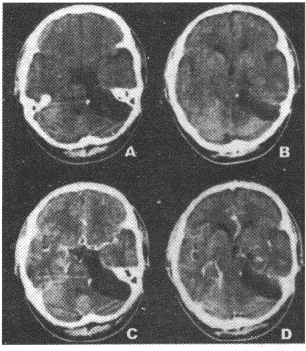

13.女性,43岁。左侧面部不适感1年。CT图像如图所示,需要进行鉴别诊断的疾病包括![]() |

| 正确答案:AD 解题思路:胆脂瘤为起源于外胚层的先天性肿瘤,是胚胎早期神经沟封闭时,皮肤外胚层的剩件留下来发展而成。 |